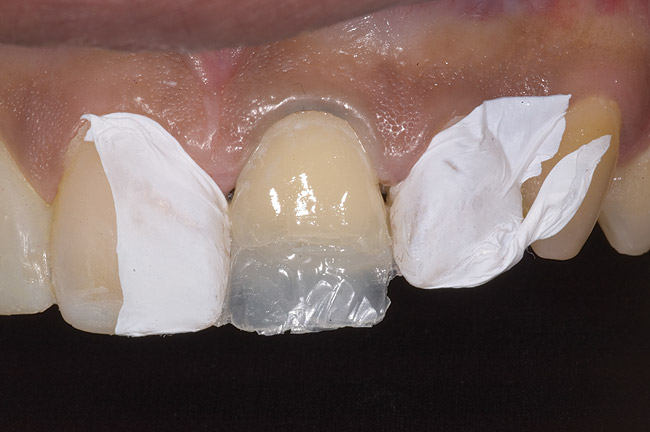

During the next appointment, a palatal index of the approved provisional was fabricated with putty silicone. This enabled the clinician to precisely build the lingual surfaces and incisal edges of teeth Nos. 6 through 11. The provisional mock-up resin on No. 9 was removed, and the underlying labial tooth was roughened with an abrasive diamond bur. No tooth structure was removed from the palatal surface, and unsupported enamel was rounded off from the labial. An ultrathin dry cord was placed in the gingival sulcus on No. 9 (Figure 9 and Figure 10). Teflon tape was used to isolate No. 9 from adjacent teeth. Then 37% phosphoric acid was used to totally etch the labial surface for 10 seconds and the palatal surfaces on No. 9 for 5 seconds. Single bond was applied and spread uniformly across the tooth and light-cured for 20 seconds.

Figure 9: Tooth No. 9 minimally prepared for resin layering on the labial surface.

Figure 9

Figure 10  Tooth No. 9 with no preparation on the palatal surface to restore lost form with bonding resin.

Figure 10